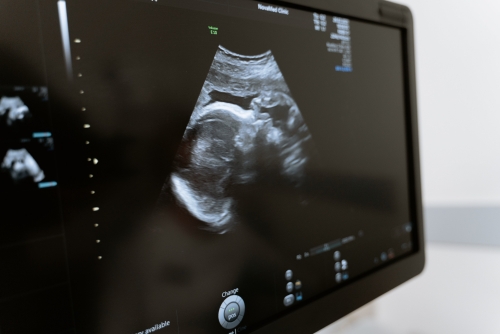

嬰兒髖關(guān)節(jié)超聲檢查,是為了檢查髖關(guān)節(jié)發(fā)育情況、測量髖關(guān)節(jié)包容間隙、觀察髖關(guān)節(jié)是否有增生、脫位、股骨頭壞死等情況。操作時(shí)一般會讓患兒取屈膝仰臥位,髖關(guān)節(jié)外展暴露,檢查者戴消毒手套,并進(jìn)行局部消毒,之后讓嬰兒處于仰臥位,雙手搭在膝關(guān)節(jié)上方,用超聲探頭對髖關(guān)節(jié)進(jìn)行檢查。

1、髖關(guān)節(jié)外展暴露:此時(shí)需暴露患兒的雙腿,將患兒的雙腿并攏,從最高點(diǎn)向內(nèi)下方進(jìn)行連線,與地面垂直,髖關(guān)節(jié)外展暴露髖關(guān)節(jié);

2、消毒:首先對髖關(guān)節(jié)局部進(jìn)行清潔消毒,然后鋪上無菌洞巾,并用超聲探頭對髖關(guān)節(jié)進(jìn)行探查,以觀察髖關(guān)節(jié)是否存在腫脹、積液、脫位、增生等情況;

超聲檢測2

3、探查:當(dāng)確定局部存在異常結(jié)構(gòu)時(shí),可對異常結(jié)構(gòu)進(jìn)行超聲探查,并明確具體位置;

4、判斷髖關(guān)節(jié)是否有增生:通過超聲檢查,還可以判斷局部是否存在囊腫、積液、股骨頭壞死等情況;

5、股骨頭壞死:通過超聲探查,可以判斷股骨頭血運(yùn)情況,以及髖臼窩是否有積液等情況。

除上述操作以外,由于嬰兒的髖關(guān)節(jié)較柔軟,在進(jìn)行超聲檢查時(shí),應(yīng)盡量選取模糊的超聲探頭,以免損傷嬰兒的皮膚。當(dāng)出現(xiàn)髖關(guān)節(jié)疾病或異常情況時(shí),需及時(shí)前往醫(yī)院就診,通過超聲檢查明確病因,并在醫(yī)生指導(dǎo)下進(jìn)行針對性治療。日常生活中可多攝入含蛋白質(zhì)、鈣豐富的食物,為嬰兒提供身體所需的營養(yǎng)物質(zhì)。